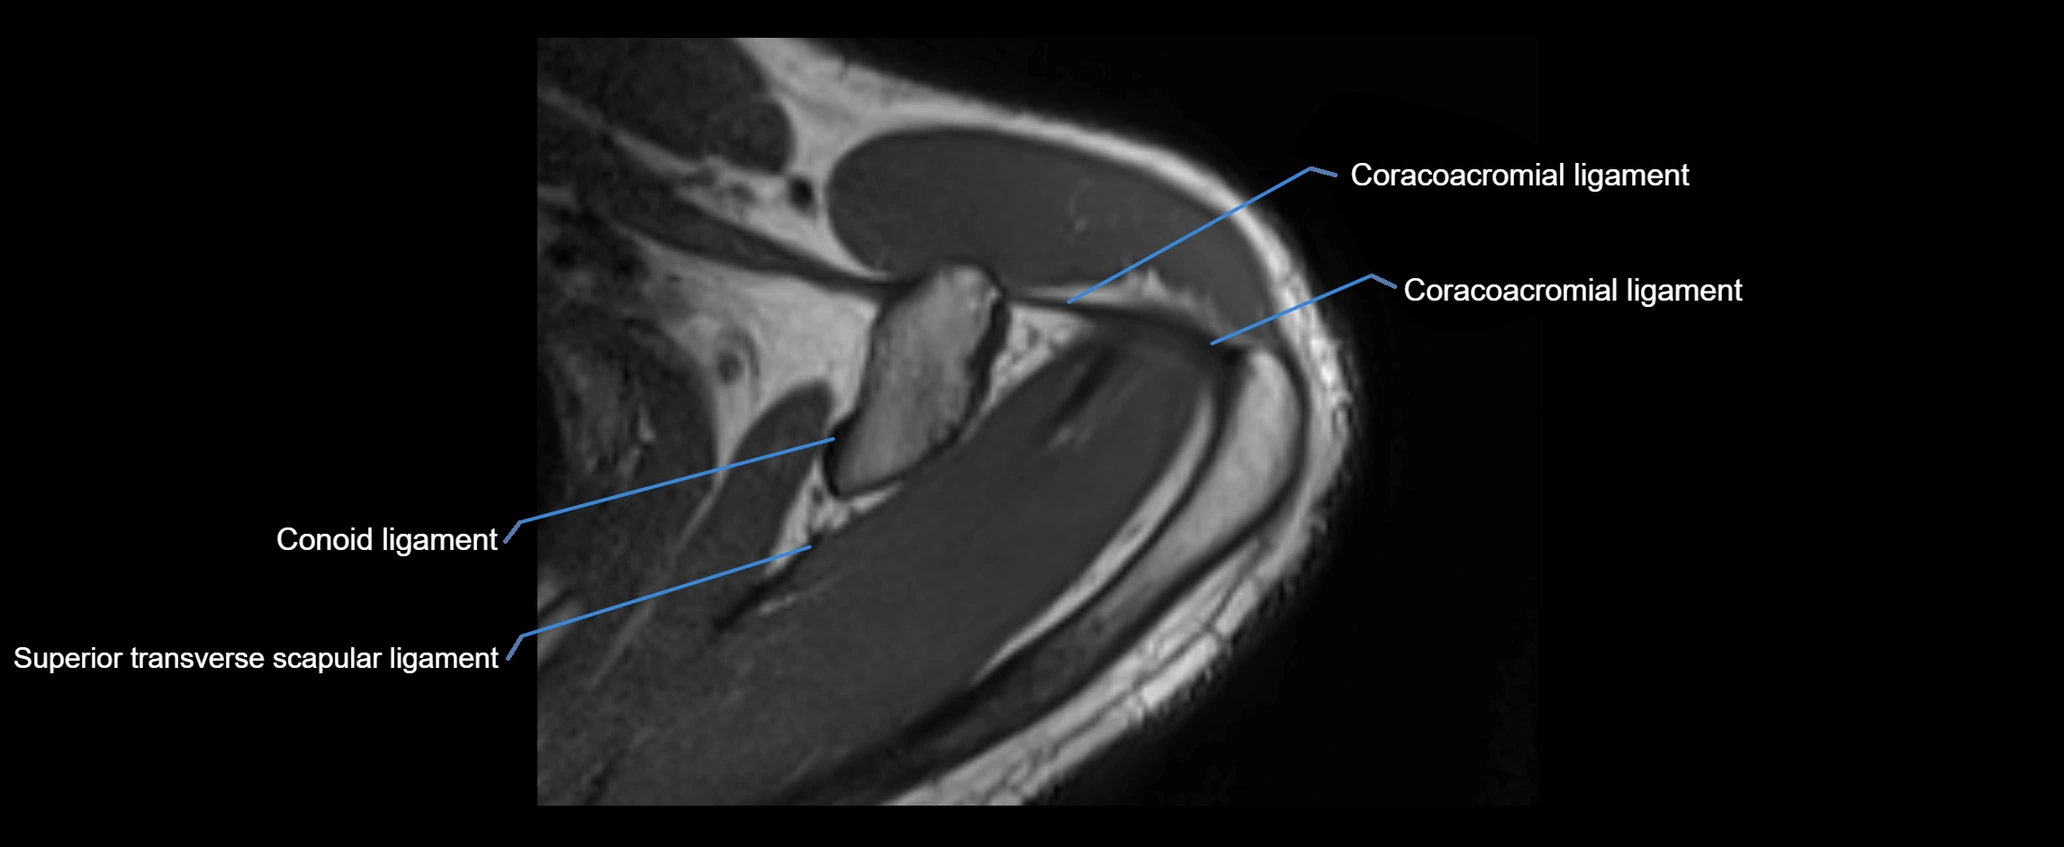

CT image

image